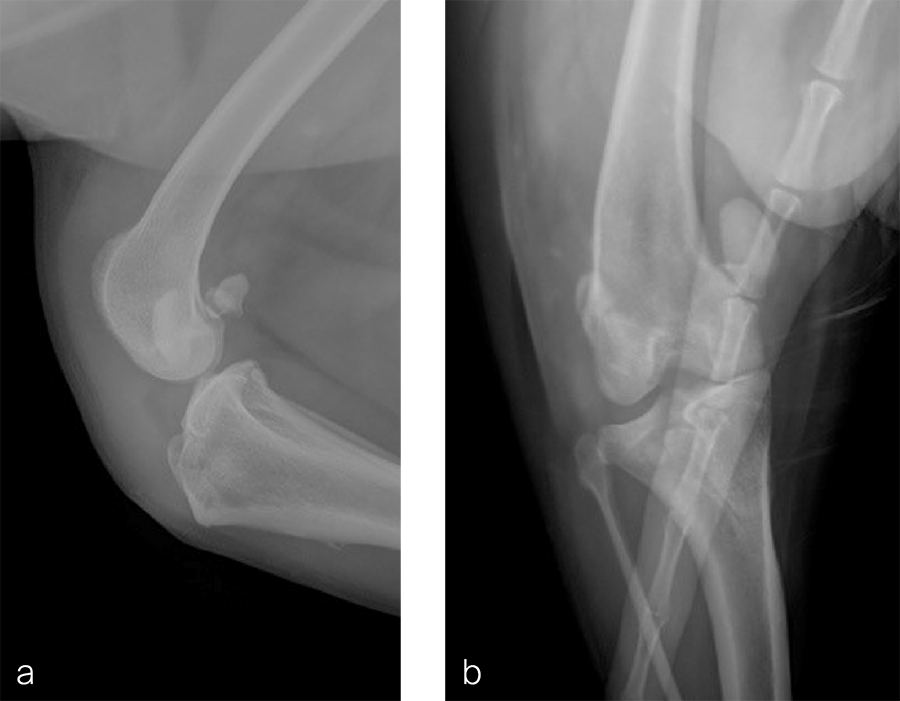

A 1.5 year old spayed female Appenzell Cattle Dog weighing 29 kg presented for a second opinion after two previous surgical procedures (Fig 7 and Fig 8) to address a traumatically induced medial patellar luxation. Orthopedic examination and preoperative radiographs revealed a grade 3/4 medial patellar luxation (Fig 8). Femoral varus was documented (aLDFA 104°; normal 92–96°) by CT scan (Fig 9 ). The planned correction was a 10° lateral closing wedge ostectomy, with concurrent sulcoplasty. Click here to read through the detailed surgical procedure.

Fig 9a-b Preoperative CT 3D reconstruction of the right femur confirming distal femoral varus (anatomical Lateral Distal Femoral Angle was 104°). Planned correction was to perform a 10° lateral closing wedge ostectomy.